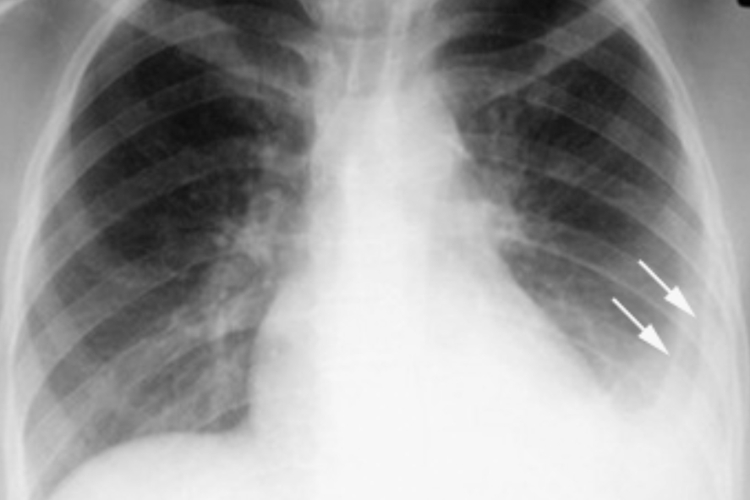

双肺索条影是放射影像中的一种表现,具体是指在肺部X光片、CT或核磁共振等影像学检查中,发现双肺存在索条状的阴影。

- 在影像学检查中发现双肺索条影时,还需要与其他肺部疾病进行鉴别诊断。特别是当索条影呈现弥漫性改变时,需要考虑到间质性肺疾病等可能性,并进行进一步检查确定病因。